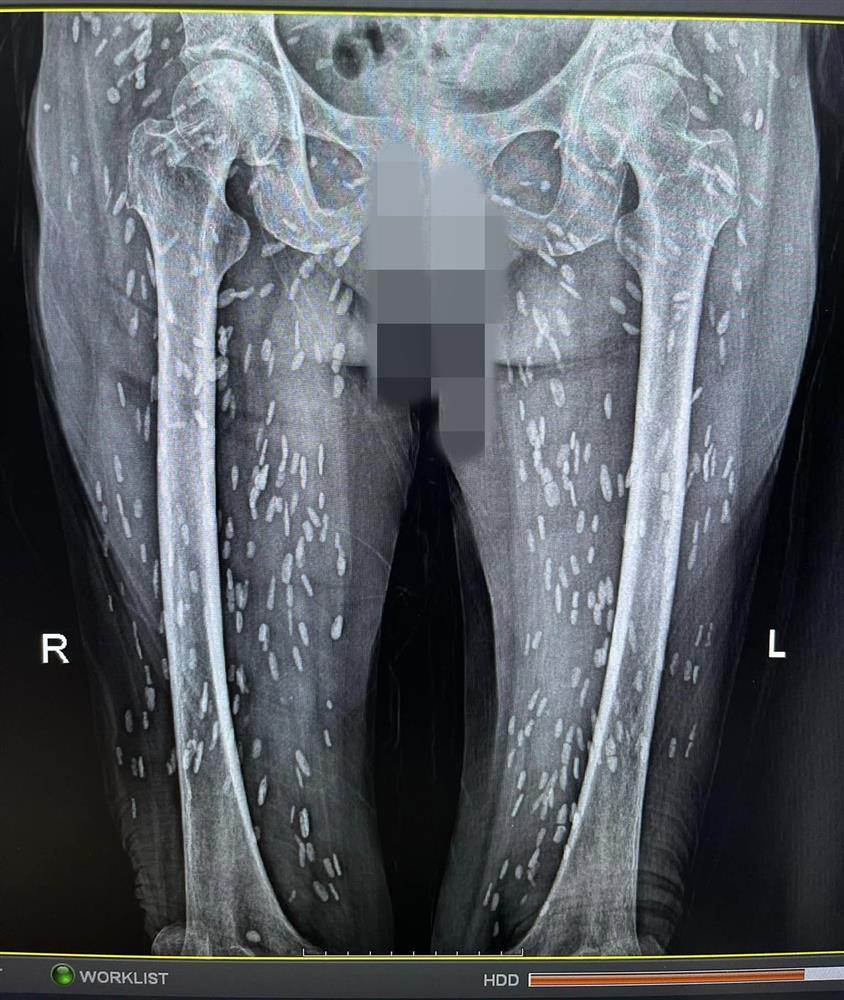

Khi đến khám, cụ được bác sĩ chỉ định thực hiện chụp X-quang. Kết quả phát hiện thấy hình ảnh nhiều kén sán hình dạng kích cỡ như hạt gạo nằm rải rác trong các mô, cơ trên phim trường vùng ngực.

Sau khi kiểm tra tổng quát thêm vùng bụng, hai chi dưới thì phát hiện thấy rất nhiều kén sán mật độ dày toàn bộ cơ thể.

Sau khi khai thác tiền sử dịch tễ cùng hình ảnh trên phim X-quang, bác sĩ chẩn đoán sơ bộ cụ bà N.T.H bị nhiễm kén sán dây lợn. Những nang kén này có thể đã tồn tại trong cơ thể người bệnh từ 5 - 7 năm.